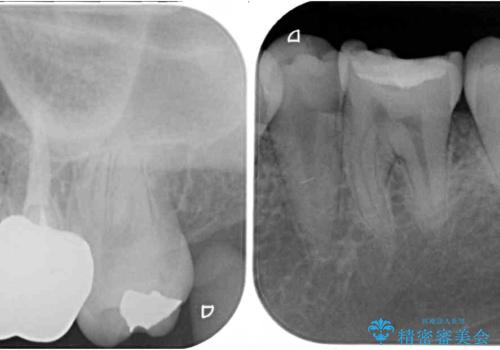

銀歯やムシ歯処置の必要な歯が奥歯にあり気になっていたので、矯正治療の途中でセラミッククラウンへ変更し、その後歯列を仕上げていくこととしました。

咬み合わせと目立っていた銀歯が改善され、患者様には大変満足していただきました。